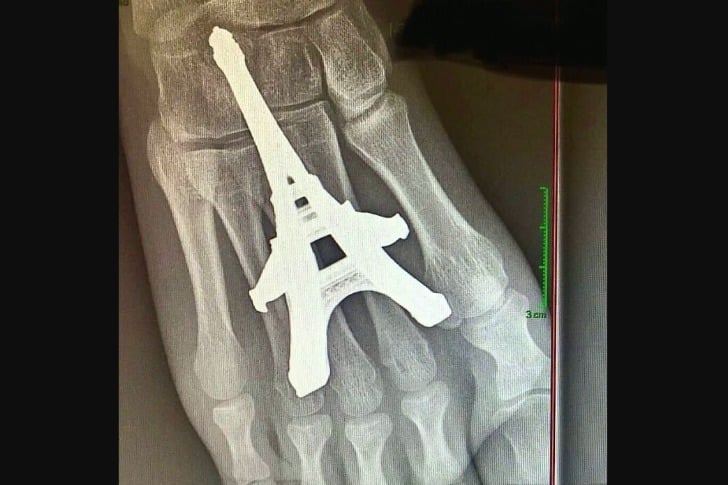

40 images médicales troublantes qui sont honnêtement terrifiantes #19 Ça a l’air douloureux ! Advertisements Comme marcher sur des Legos, mais en pire. Advertisements PrécédentPage suivante Advertisements PREV NEXT PAGE